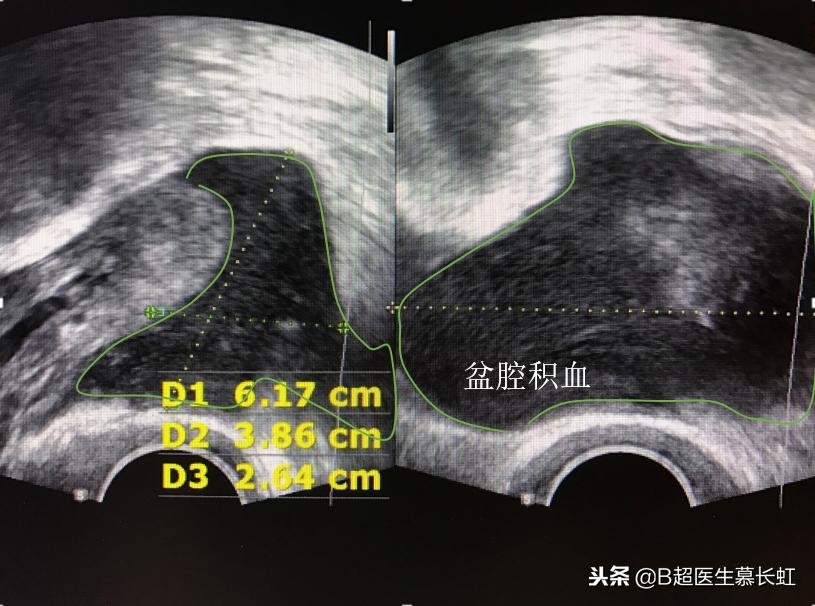

盆腔积血(此图为宫外孕引起)

b 宫外孕或黄体破裂:当看到盆腔积液的液体不够清亮,液体中有细点状回声或絮状回声时,那么可能所积液体是血液,叫积血。这时候超声医生会仔细为你检查,结合你的月经时间,临床症状(比如宫外孕的话可能会有少量阴道出血;黄体破裂的话会有下腹部剧烈疼痛),结合HCG检测,然后再查看是否盆腔内有可疑宫外孕包块或者黄体破裂的超声征象。如果是这个原因,那么就要由临床妇科医生来判断整个病情,看看是保守药物治疗,还是立即手术。